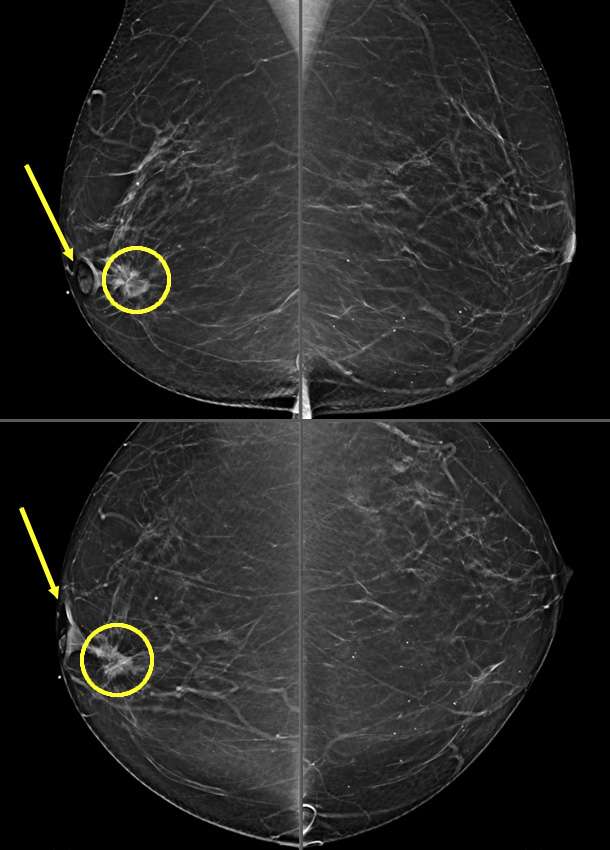

- Mammography: Skin retraction may be noted as an irregular, pulled appearance of the skin. An underlying mass may or may not be mammographically visible.

- Ultrasound: May further reveal distortion in the skin layers but is most helpful in further evaluating the presence of an underlying mass causing the retraction.